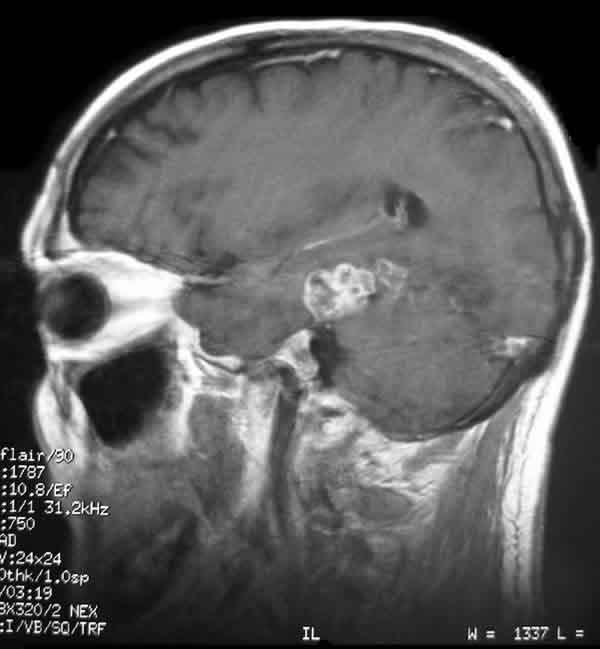

Fig. 1: Imagen de la RMN craneal que muestra una lesión ocupante de espacio en el lóbulo temporal izquierdo posterior.